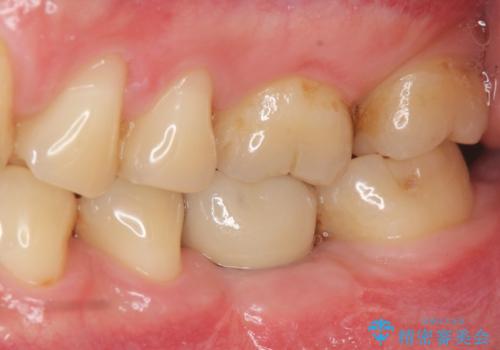

- 銀歯の奥歯で噛むと違和感・痛みがあるとのことで検査・治療を求めて来院されました。

銀歯を除去して見ると内部で虫歯が再発し、歯の辺縁は破折し保存が難しく抜歯をしなければいけない状態でした。